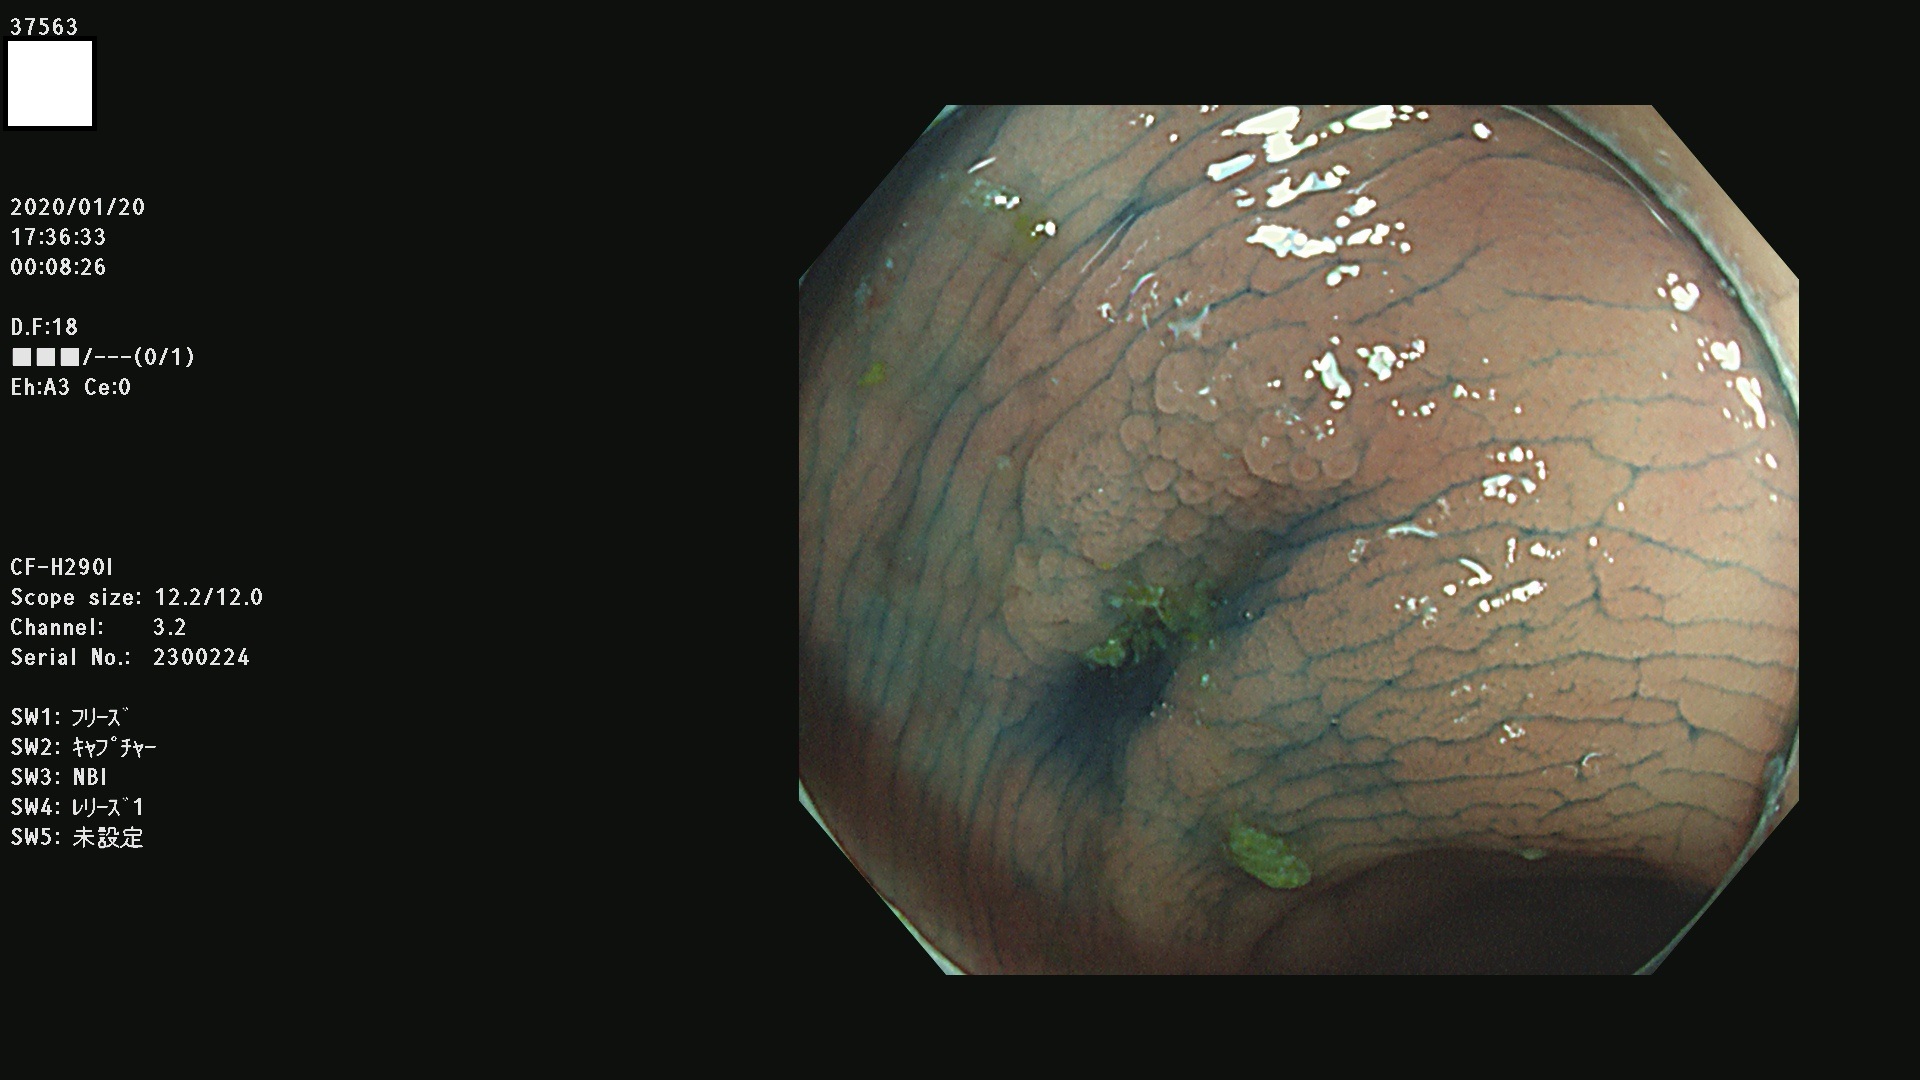

腺腫発見率 67 % (カルテ番号 37500〜37599の100名の方の検査結果で集計)大腸癌検診最新情報

以下のカルテ番号の方に腺腫(Adenoma,Group3〜5)が見つかりました(集計法)

37500 37502 37503 37505 37508 37509 37510 37511 37512 37513 37514 37517 37519 37520 37521 37525 37526(SSAPのみ) 37527 37528 37529 37531 37532 37533 37534 37536 37538(SSAPのみ) 37539 37541 37542 37543 37547 37548 37549(SSAPのみ) 37550 37552 37555 37556 37561 37562 37563(SSAPのみ) 37564 37565 37566 37567 37568 37570 37571 37572 37573 37574 37575(SSAPのみ) 37576 37577 37579 37580 37582 37583 37586(SSAPのみ) 37587 37588(SSAPのみ) 37590 37593(SSAPのみ) 37594 37596 37597(SSAPのみ) 37598 37599

発見困難で危険性の高い平坦型病変(上記100名より抽出) ![]()